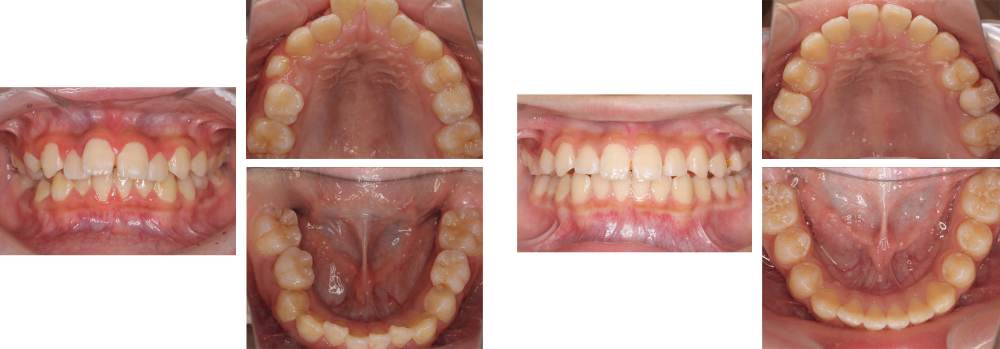

小児矯正

術前

術後

| 治療内容 | 叢生に対して床矯正を使用し治療を行った |

|---|---|

| 治療期間・回数 | 20カ月間・19回(動的治療まで) |

| 費用 ※自由診療となります |

矯正検査①:33,000円 床装置(ネジあり):77,000円 ×2 床装置(ネジなし):55,000円 ×2 |

| リスク・副作用 |

|